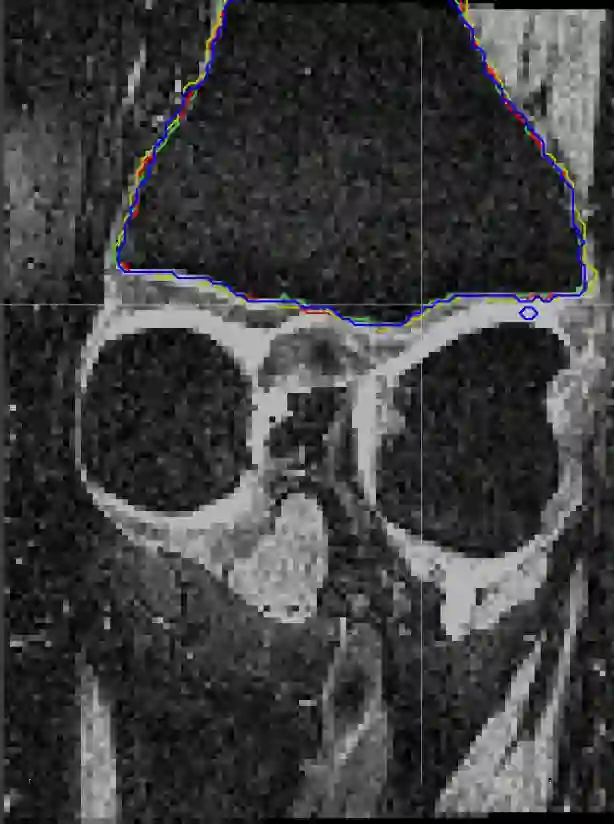

Direct automatic segmentation of objects from 3D medical imaging, such as magnetic resonance (MR) imaging, is challenging as it often involves accurately identifying a number of individual objects with complex geometries within a large volume under investigation. To address these challenges, most deep learning approaches typically enhance their learning capability by substantially increasing the complexity or the number of trainable parameters within their models. Consequently, these models generally require long inference time on standard workstations operating clinical MR systems and are restricted to high-performance computing hardware due to their large memory requirement. Further, to fit 3D dataset through these large models using limited computer memory, trade-off techniques such as patch-wise training are often used which sacrifice the fine-scale geometric information from input images which could be clinically significant for diagnostic purposes. To address these challenges, we present a compact convolutional neural network with a shallow memory footprint to efficiently reduce the number of model parameters required for state-of-art performance. This is critical for practical employment as most clinical environments only have low-end hardware with limited computing power and memory. The proposed network can maintain data integrity by directly processing large full-size 3D input volumes with no patches required and significantly reduces the computational time required for both training and inference. We also propose a novel loss function with extra shape constraint to improve the accuracy for imbalanced classes in 3D MR images.